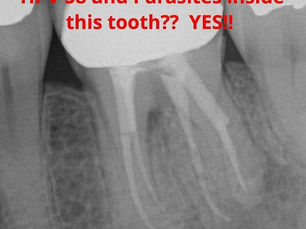

Can HPV and Parasites Hide in Your Dead Teeth?

By Blodgettdentalcare Toxic Tuesday: Can HPV and Parasites hide in your dead teeth? Based on the findings recent tests performed in our...